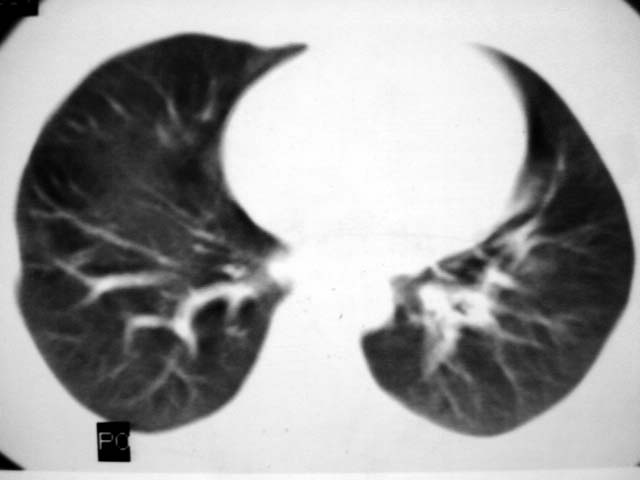

标题: CT12463:女,19岁,炎性假瘤?结核球? [打印本页]

女,19岁,体检时发现。炎性假瘤?结核球?

早产儿,幼时体弱,常感冒肺部感染,13岁后好转。两月前“感冒”后咳嗽两周。

首先要说ct机太差,片子质量不佳,一定是2秒以上机器的作品!其次ct技师需进一步培训,象这种情况就应该针对病灶部位做薄层或高分辨扫描。不过从上传影像看,患者年轻、病灶周围没卫星灶倒支持炎性假瘤诊断,不过象这种部位也有可能是叶间包裹性积液可能。只是ct机太、太差,很难诊断,如一秒机扫描出来90%可直接诊断,有必要时可结合矢状位三维重建。所以要我说建议患者在亚秒(至少是1秒)机上重扫十分有利于正确诊断。

考虑炎症,抗炎后复查。理由:病变肺窗显示的大小明显大于纵隔窗,提示病变周围为密度偏低的渗出改变。不同于结核球和肿瘤。